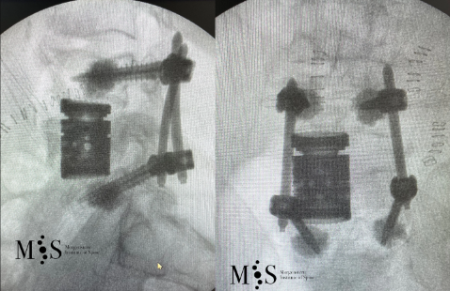

Percutaneous stabilization of unstable vertebral fractures

In cases of complex (unstable, burst, etc.) vertebral fractures, additional stabilization of the fracture by percutaneous stabilization is usually required. In cases where there also is a neurological deficit (muscle weakness, tingling in legs or arms, etc.), a decompression of the spinal canal is additionally required. A percutaneous stabilization of the spine with screws and rods discharges the load on the unstable fracture, stabilizing the whole spine and relieving pain. Depending on the patient’s bone quality, the stabilized vertebrae may be additionally cemented by kyphoplasty.

Vertebral body resection (corpectomy) and reconstruction of complex vertebral and burst fractures

Severe vertebral body fractures, i.e. conminute and burst fractures, may require a partial vertebral body resection (corpectomy) and reconstruction with an expandable vertebral body cage. Especially severe fracture cases are also those with a bone fragment moving into the spinal canal that compresses on neural structures, such as the spinal cord and causes spinal canal stenosis. Corpectomy allows to resect most of the fractured body, including the bone fragments pushing on the nerves and intruding into the spinal canal. The vertebral body reconstruction is usually rounded up with a posterior augmented instrumented fusion of the adjacent levels to the fracture. All of this allows a proper healing of the fracture and the patient to recover without pain.

Clinical case example of a lumbar vertebral body resection (corpectomy) and reconstruction of a burst fracture at level L4.